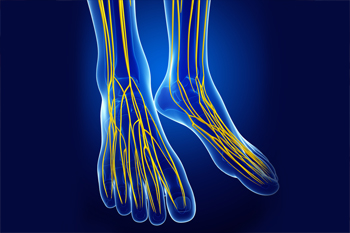

Causes of Nerve Pain in the Feet

Nerve pain in the feet often develops when the nerves that carry signals from the spine to the toes become damaged or compressed. This pain can feel like burning, tingling, numbness, or electric-like shocks. Problems in the lower back, such as a herniated disc or spinal stenosis, can irritate nerves that extend into the feet. Peripheral neuropathy, which occurs when nerves in the legs or feet themselves are injured, can also lead to discomfort, weakness, and loss of sensation. Diabetes, traumatic injuries, and prolonged pressure on the feet can all contribute to nerve damage. Footwear that lacks adequate support, repetitive strain, or prolonged standing can worsen symptoms by increasing nerve compression. A podiatrist can perform diagnostic tests to locate the source of the pain and provide treatment that helps protect nerve health and restore comfort. If you have symptoms of nerve pain in the feet, it is suggested that you schedule an appointment with a podiatrist for a diagnosis and appropriate treatment options.

What Is Neuropathy?

Neuropathy is a condition that leads to damage to the nerves in the body. Peripheral neuropathy, or neuropathy that affects your peripheral nervous system, usually occurs in the feet. Neuropathy can be triggered by a number of different causes. Such causes include diabetes, infections, cancers, disorders, and toxic substances.